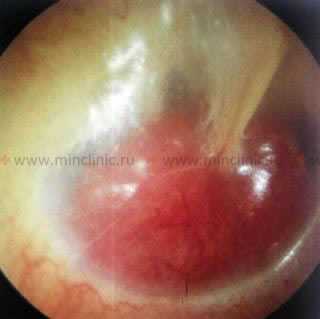

Гнойный отит или воспаление среднего уха. Сквозь барабанную перепонку просвечивается уровень воспалительной жидкости (гноя) красного цвета.